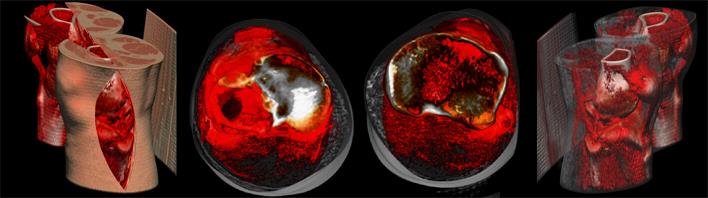

- 模擬病人骨折,讓醫(yī)生更直觀的了解骨折情況

- 軟件模擬手術入路,為醫(yī)生選擇最佳入路提供參考

該手術在軟件的輔助下確定以不剔除腓骨的方式進行手術